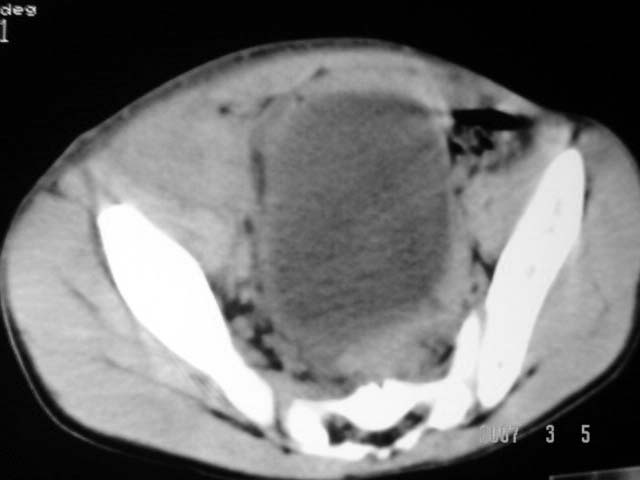

以下是引用dyqct在2007-3-5 10:28:00的发言:[br]右髂窝肿块。[br][br][br][br]